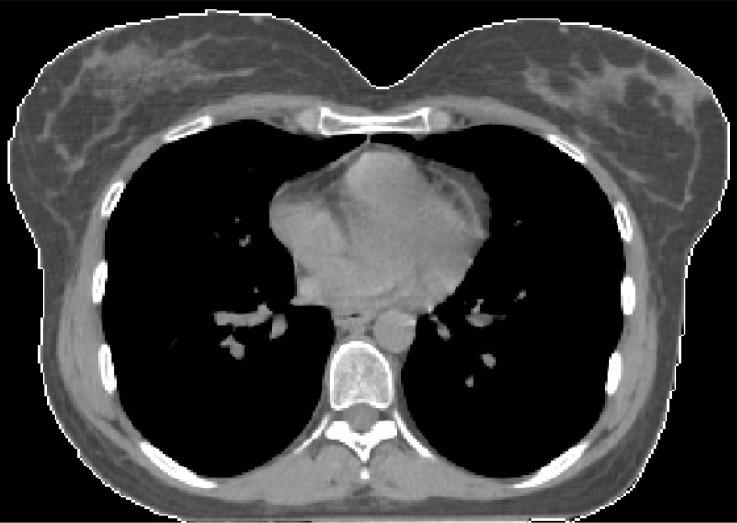

The patient was a 33-year-old female with diagnosis of T-ALL. She received intensive systemic chemotherapy that resulted in complete remission of her disease, and then underwent allogeneic hematopoietic stem cell transplantation. After a 15 mo period without symptoms and signs of progression, the patient presented with palpable masses in both breasts. She complained from severe pain and swelling of the breasts. Imaging workup showed bilateral breast lesions, and diagnosis of breast infiltration by leukemic cells was confirmed after immunohistopathological evaluation. The patient suffering from severe pain, discomfort, and swelling of both breasts due to leukemic infiltration was referred to the Radiation Oncology Department for symptomatic palliation. Whole breast irradiation was delivered to both breasts of the patient with BART using the ABC system. The patient had complete resolution of her symptoms after treatment with BART.

BART with the ABC system resulted in complete resolution of the patient's symptoms due to leukemic infiltration of both breasts with T-ALL. This contemporary treatment technique should be preferred for radiotherapeutic management of patients with leukemic infiltration of the breasts to achieve effective symptomatic palliation.